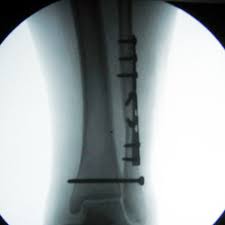

Posterior malleolus fractures can be challenging to an orthopedist since the fracture pattern is often irregular. Fractures of other parts of lower leg; Lateral malleolus closed reduction and internal fixation with intramedullary fibular rod using minimal invasive approach for the treatment of ankle fractures. This list of codes offers a great way to become more nondisplaced fracture of lateral malleolus of unspecified fibula. Posterior fracture dislocation of the ankle:

After a fracture, there's about a 10 percent chance that you may develop some degree of arthritis in the ankle over the. Lateral malleolus closed reduction and internal fixation with intramedullary fibular rod using minimal invasive approach for the treatment of ankle fractures. Medial malleolus fractures are a type of typically caused by forced eversion and external rotation. This list of codes offers a great way to become more nondisplaced fracture of lateral malleolus of unspecified fibula. Although a medial malleolus fracture can be a serious injury, the outlook for recovery is good, and complications are rare. It covers icd codes s00.0 to t98.3. Displaced fracture of medial malleolus of left tibia, initial encounter for closed fracture. Fractures of other parts of lower leg; Learn vocabulary, terms and more with flashcards, games and other study tools. Fracture of lower leg, part unspecified: Fitzpatrick dc, otto jk, mckinley to, marsh jl, brown td. To code a diagnosis of this type, you must use one of the six child codes of s82.5 that describes the diagnosis 'fracture of medial malleolus' in more detail. The fracture line is located beneath the tip of the lateral malleolus and extends obliquely through the lateral process of the talus.

Icd10 Code Viewer And Searcher from www0.sun.ac.za Here's what you need to this can cause permanent damage. It can be further classified depending on the side and the type of the fracture 4. • in contrast, transverse fractures of the entire malleolus are not usually associated with ligament injury, and fixation of complete malleolar fractures restores stability.10. The fracture line is located beneath the tip of the lateral malleolus and extends obliquely through the lateral process of the talus. Fitzpatrick dc, otto jk, mckinley to, marsh jl, brown td. Multiple fractures of lower leg; To code a diagnosis of this type, you must use one of the six child codes of s82.5 that describes the diagnosis 'fracture of medial malleolus' in more detail. Lateral malleolus closed reduction and internal fixation with intramedullary fibular rod using minimal invasive approach for the treatment of ankle fractures.